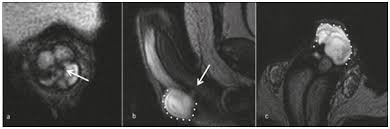

Patients usually present with a smooth cord-like induration on the dorsal penile shaft 1-7 days after prolonged or intensive sexual intercourse but other presentations of disease and triggers for endothelial damage are possible.

Medical therapy may also be indicated which typically involves aspirin or oral anticoagulants until the thrombophlebitis resolves. Pain is one of the first symptoms of penile thrombosis a man may notice. Thrombectomy and resection of the superficial penile vein are applied surgically in the patients refractory to the medical treatment. Subacute forms have been treated with anti-inflammatory drugs and local heparinized cream. Patients usually present with a smooth cord-like induration on the dorsal penile shaft 1-7 days after prolonged or intensive sexual intercourse but other presentations of disease and triggers for endothelial damage are possible. These Read more. Over the counter pain relievers are prescribed to reduce pain and inflammation.